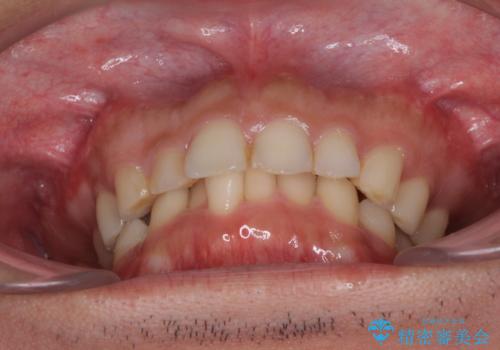

- 深い咬み合わせと前歯のデコボコ、奥歯の欠損を気にして来院された患者様です。

歯列矯正はインビザラインを使用し、矯正治療中の適切な時期に奥歯の欠損部位にインプラントを埋入することとしました。